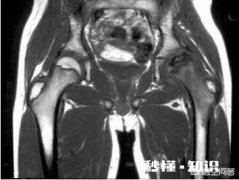

- 髋关节结核是什么病是由什么引起的